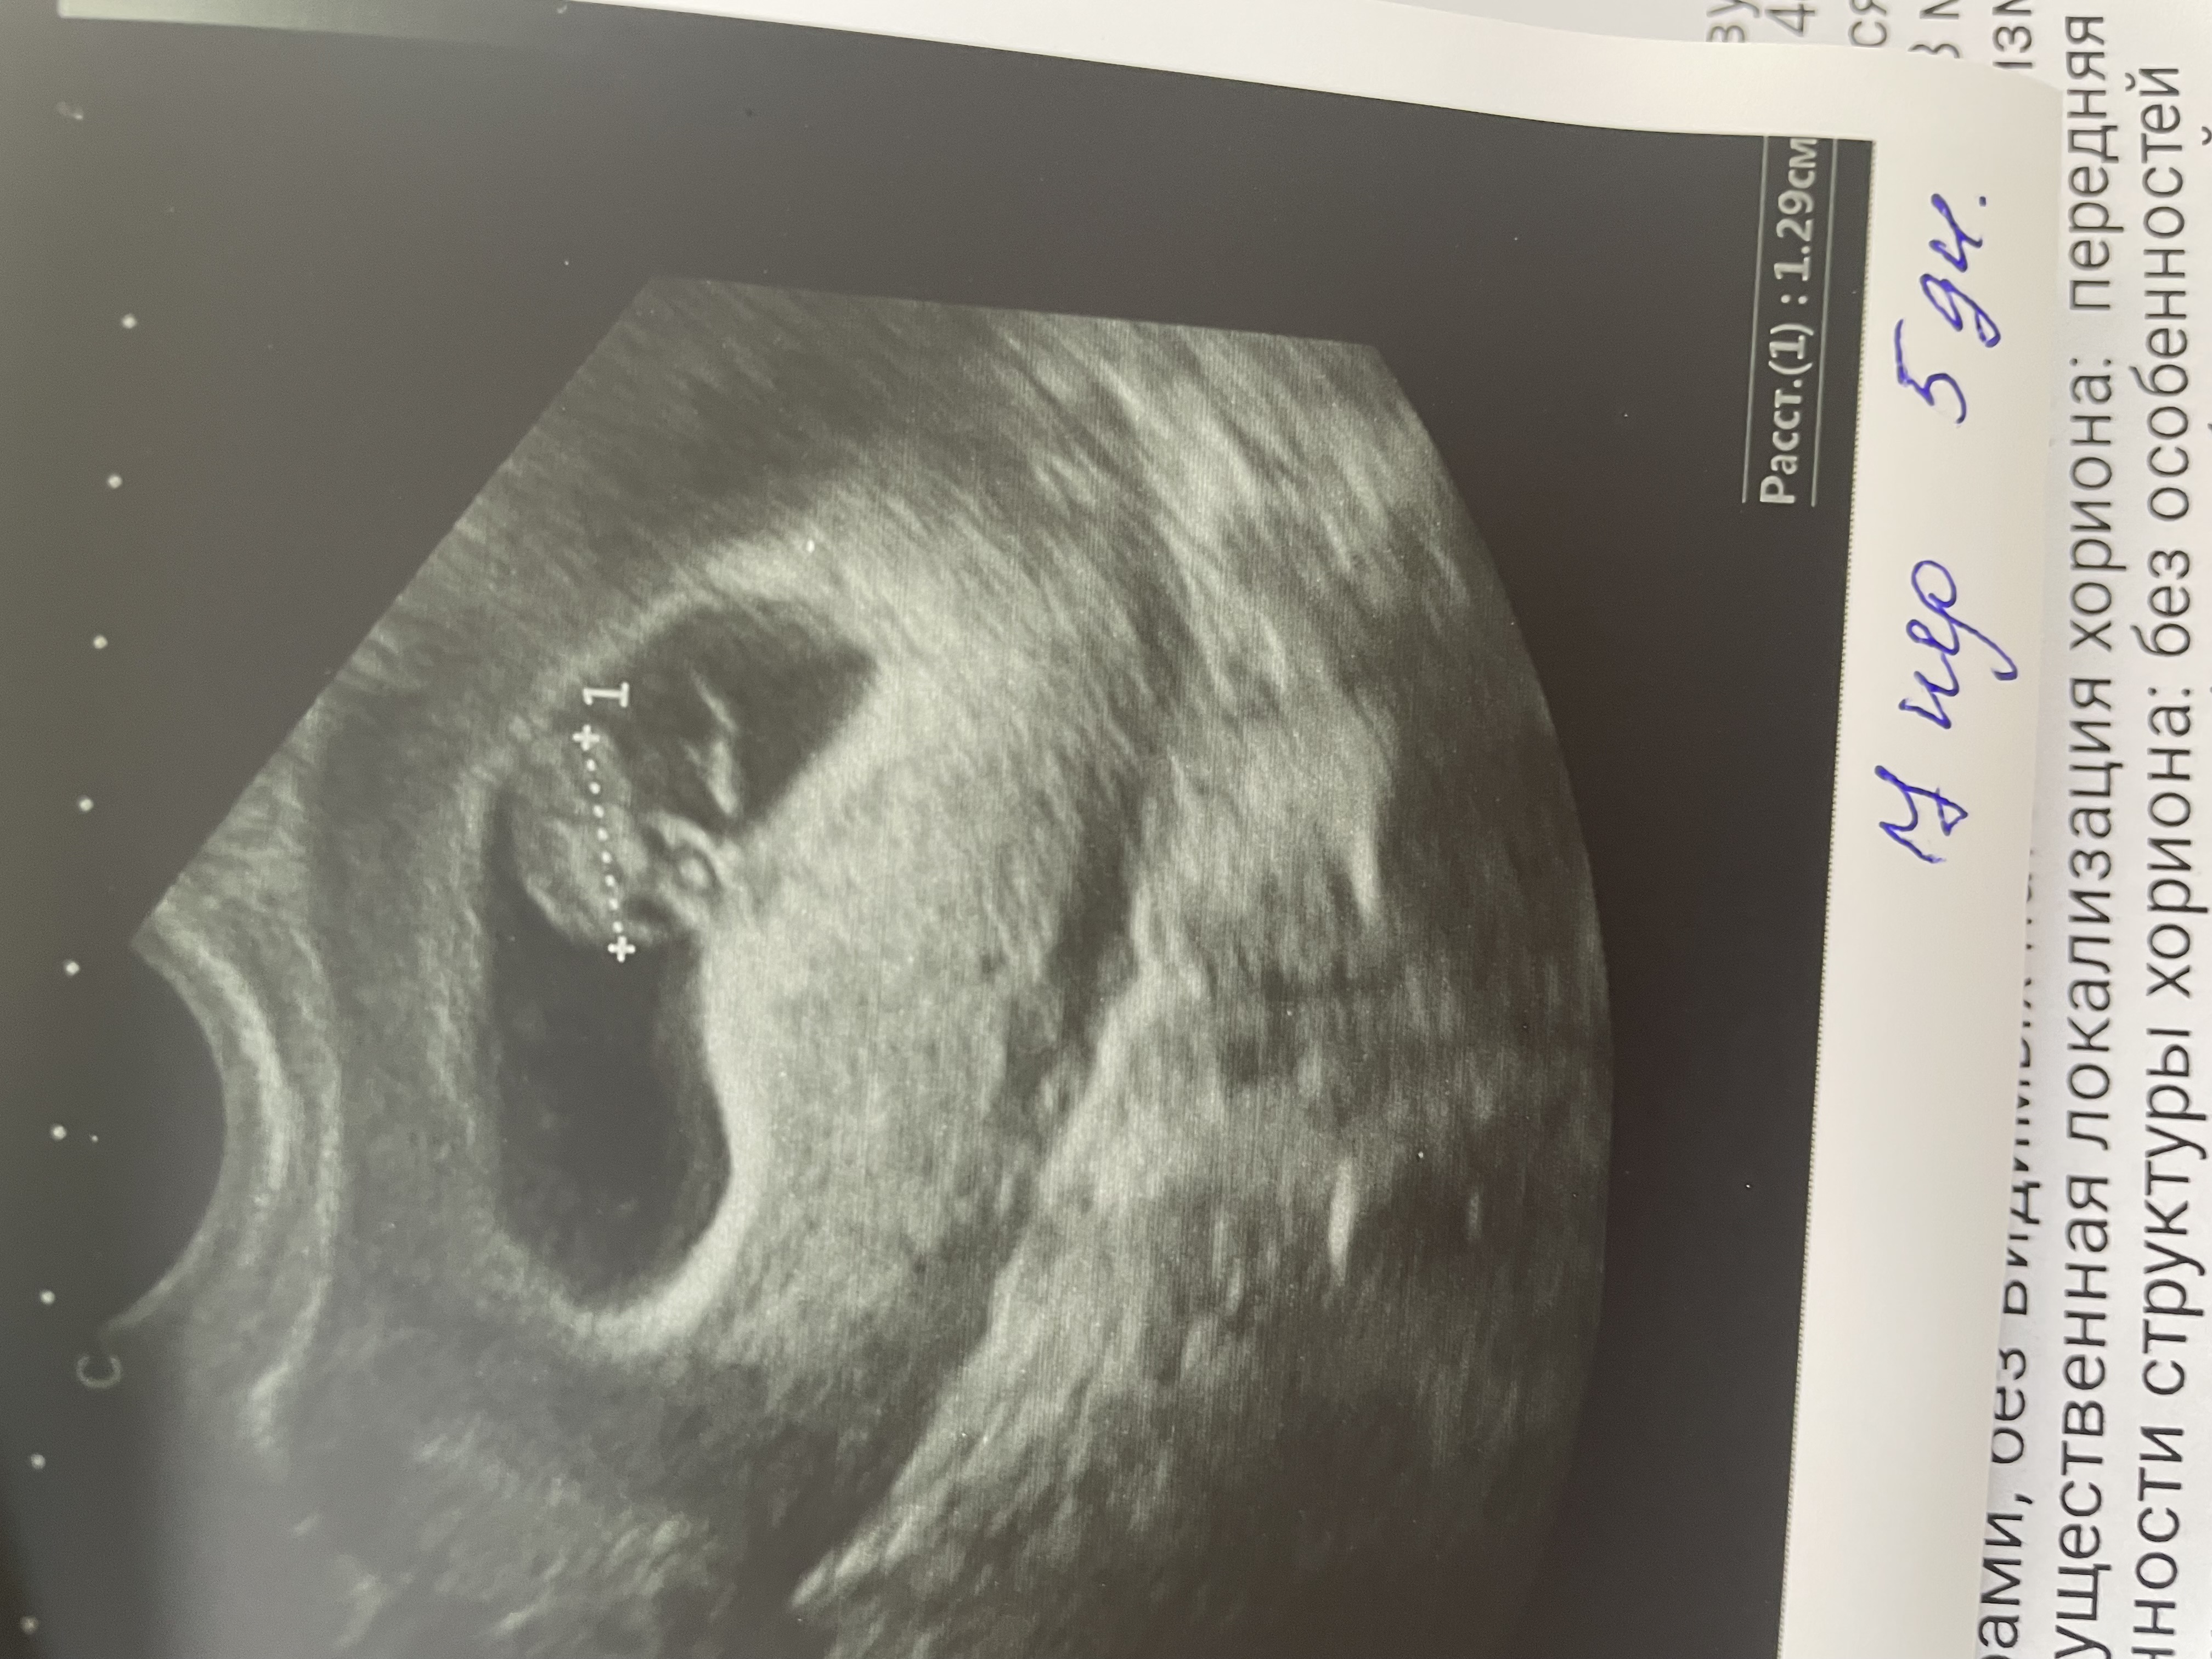

Растут мои крошки 💕✨🤰

у меня двойня!!!!!!! Вторая двойня подряд